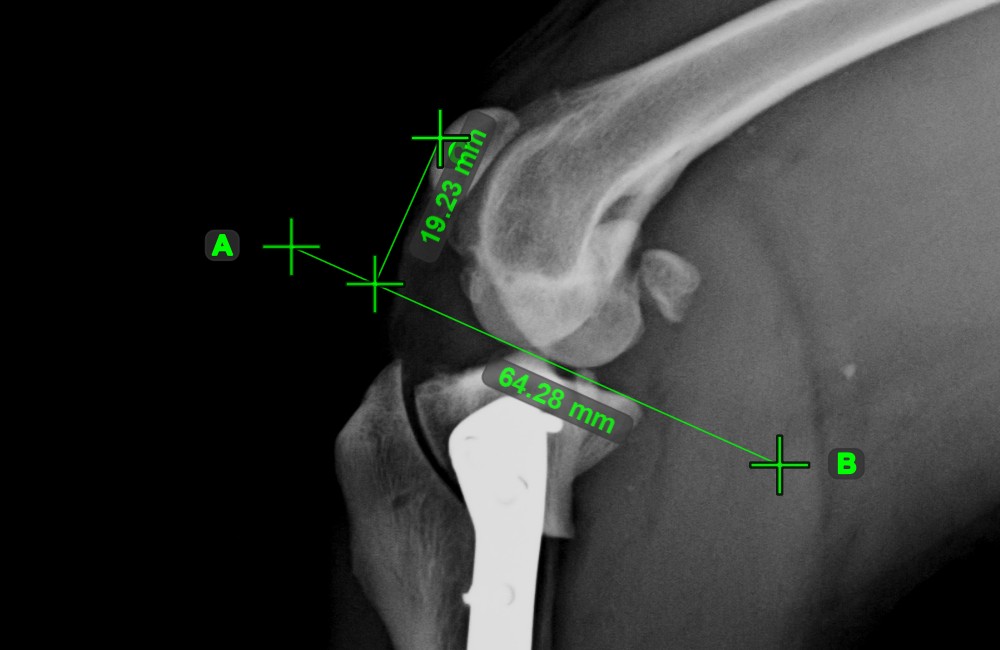

Linienmessung¶

Erstellen Sie eine Linienmessung, um den Abstand zwischen zwei Punkten mit hoher Genauigkeit zu berechnen.

Wählen Sie das Werkzeug Linienmessung

aus und weisen Sie es einer der verfügbaren Maustasten zu. Setzen Sie die Start- und Endpunkte in der Szene oder wählen Sie sie aus bereits vorhandenen Punkten im Bild aus. Der Abstand zwischen den beiden Punkten wird automatisch anhand der Standardkalibrierdaten oder der durch die Längenkalibrierung-Messung neu kalibrierten Daten berechnet.

Ändern Sie den Start- und Endpunkt mit dem Werkzeug Objekt auswählen/verschieben

. Der Abstand zwischen den beiden Punkten wird automatisch neu berechnet.